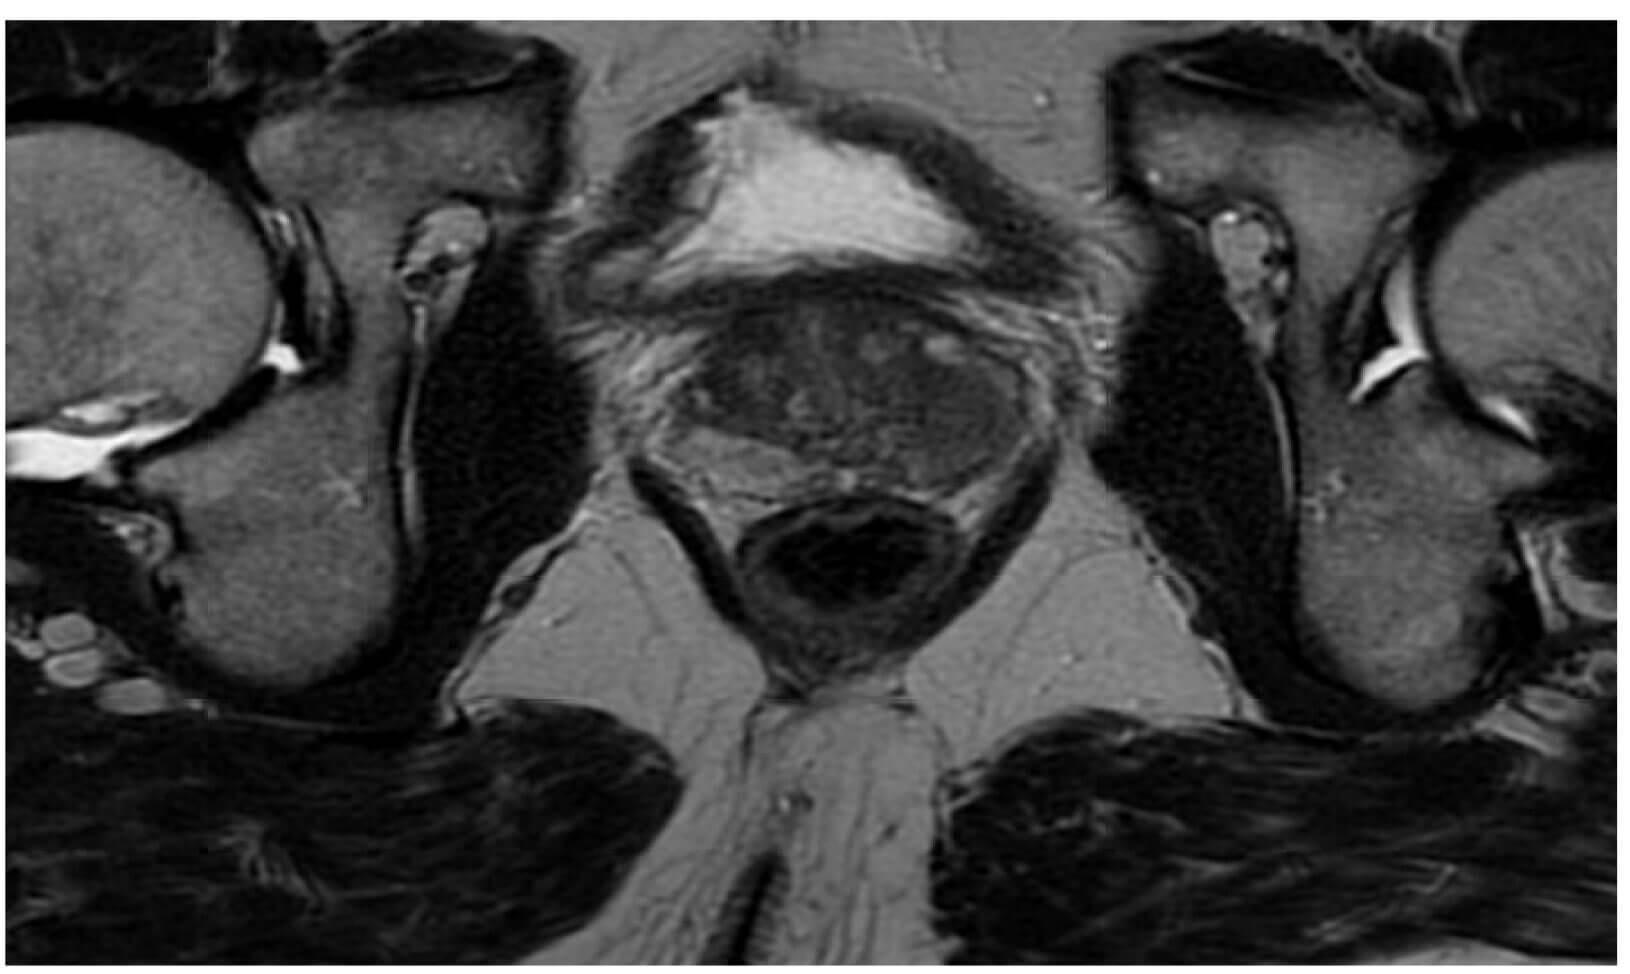

A 70-year-old male of white ethnicity had been diagnosed with unfavourable intermediate risk prostate cancer on a background of his GP checking his prostate specific antigen (PSA), which was 9.8, as part of a routine health check. He was deemed to have an excellent performance status, with a body mass index of 24. He had no pre-existing lower urinary tract symptoms nor history of previous abdominal surgery. Since his MRI (Figure 1a and 1b) staged him as T3a N0, along with Gleason 4+3 prostate acinar adenocarcinoma, he underwent a prostate-specific membrane antigen (PSMA) PET staging scan. This scan confirmed organ confined prostate cancer. The patient elected to undergo a RARP which took place four months after his transperineal prostate biopsy.

Figure 1a: Pre prostate biopsy MRI pelvis. T2 sequence showing anatomy of the prostate.

Figure 1b: Pre prostate biopsy MRI pelvis. T2 sequence showing anatomy of the pubic symphysis.